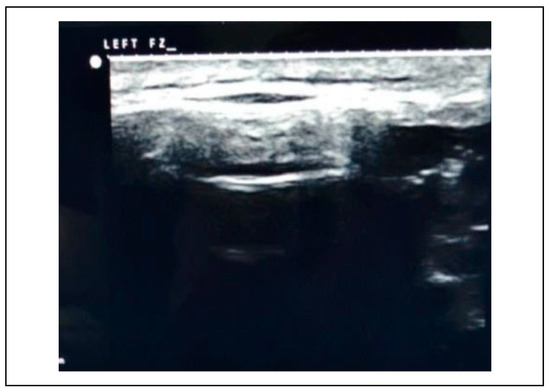

Ultrasonographic examinations were done before reduction, after reduction and after fixation at the frontozygomatic region, infraorbital rim and zygomatic buttress (refer Figure 3, Figure 4, Figure 5, Figure 6, Figure 7, Figure 8 and Figure 11, Figure 12 and Figure 13). The observations were entered on a Microsoft Excel (Microsoft Office Excel 2007 MSO12.04518.1014) spreadsheet with columns and rows (Table 1 and Table 2).

Figure 3.

Preoperative USG—infraorbital rim.

The subjects of the study group underwent an ultrasonographic examination before reduction at the frontozygomatic region, infraorbital rim and zygomatic buttress to assess the discontinuity of the bony fractured margins which were surface marked using a dermi marker at the respective points (Figure 3, Figure 4, Figure 5). These points served as landmarks to assess the reduction of the fracture site post reduction and fixation.